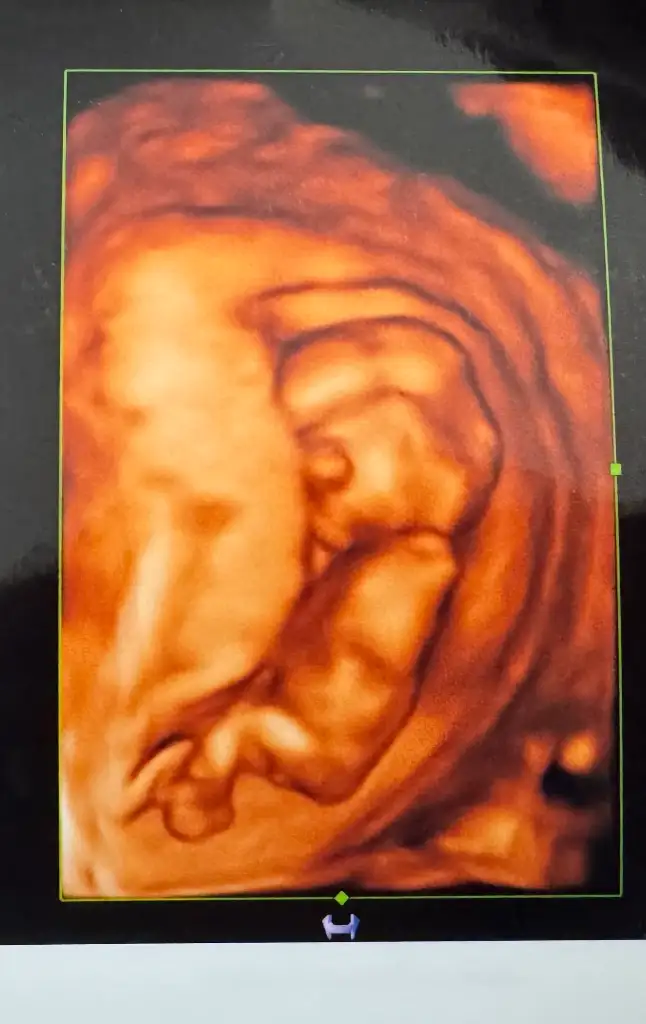

Tahmini olan varmı ? Banada bi yorum yapsanız doktor yüzde 70 erkek dedi ama chatGBT kız diyor nub teorisine göre. 2 tane oğlum var Buda kız olsun çok istedik. Yüzde 70 dedi içimde hâlâ bi umut var sanki

Eklentiler

• C05942FF-137E-43CF-BE8C-3B4CD554D2C8.webp

22,8 KB · Görüntüleme: 15

Allah bağışlasın ama sanki erkek gibi,erkekse kızı bulana kadar devam mı yoksa adaya veda eder misinizbir de ben bir yazı okumuştum,kimi çiftler kız bebege kimi de erkek bebeğe genetik olarak daha yatkın oluyormuş,ondan mütevellit 6-7-8-9...kız bir oğlan ya da tam tersi oluyormuş ,hakikaten de öyle bir çiftin 6 erkekse ya da ne bileyim 6 erkek bir kızsa.ancak genetik yatkınlık la açıklanabilir

kızlaar bugün doktor kontrolüm vardı çok şükür herşey yolunda, fetal için kan verdik 1 haftaya çıkacakmış sonuç. Doktorum cinsiyette bi tahmini olduğunu söyledi ama organizasyon yapmak istediğimizi söyleyince fetali bekleyelim net olsun dedi. Ama eğlence olsun ultrason fotoğrafından tahmin eder misiniz sizce kız mı erkek mii

• IMG_4552.webp

44,9 KB · Görüntüleme: 0

• IMG_4551.webp

23,3 KB · Görüntüleme: 0

• IMG_4547.webp

35,8 KB · Görüntüleme: 0